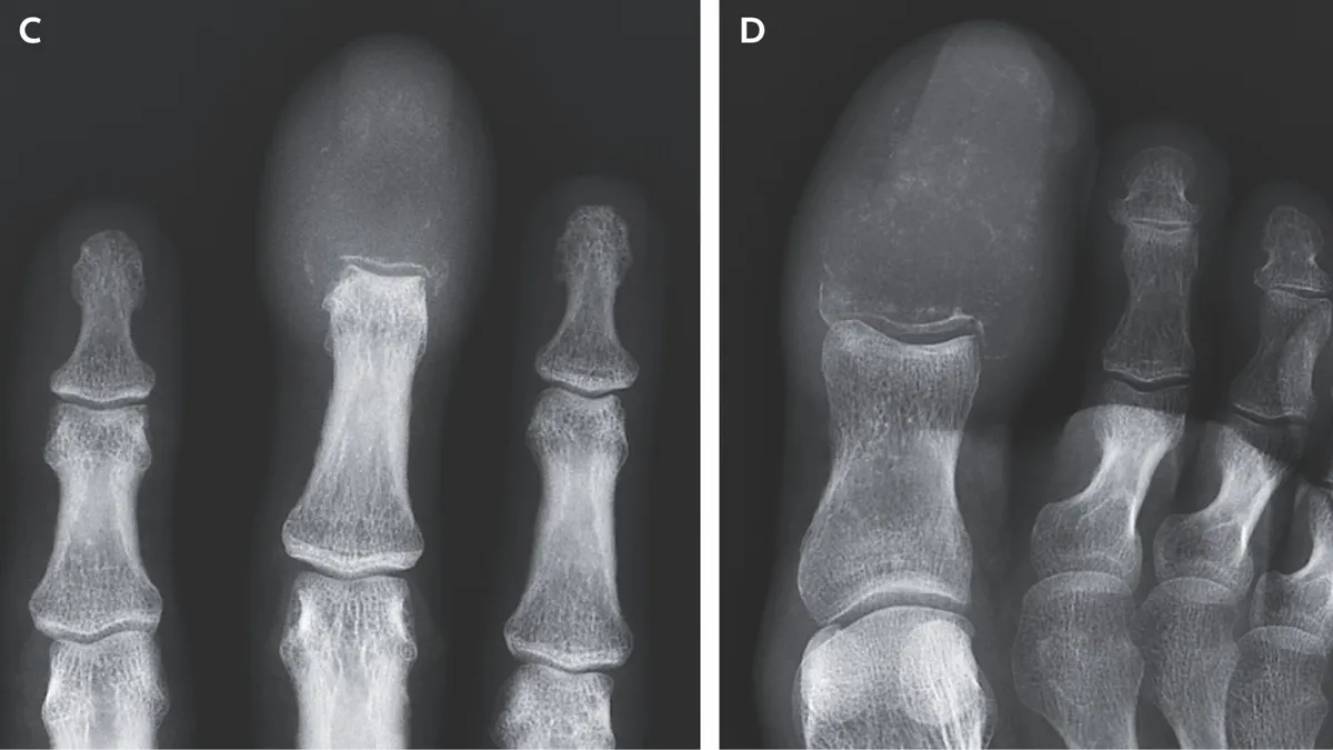

Le choc des radiographies : des os littéralement 'mangés' par la maladie

Et puis, les radiographies sont arrivées. Et là, le choc. Les images ont révélé une réalité terrifiante. Le cancer avait créé ce que les médecins appellent des ‘lésions lytiques destructrices’. En termes simples, cela veut dire que le cancer avait littéralement ‘mangé’ l’os, le remplaçant complètement. Au bout de son doigt et de son orteil, il n’y avait plus d’os sain, juste des trous, des zones vides laissées par la maladie.